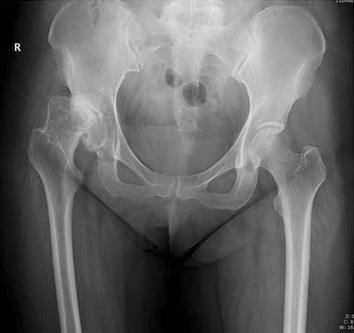

Malformation congénitale ou développementale de l'acétabulum qui ne couvre pas suffisamment la tête fémorale, entraînant une instabilité et une arthrose précoce.

Ostéotomie fémorale

Fréquente chez les patients âgés ostéoporotiques après chute. Urgence chirurgicale dont le traitement dépend du déplacement, de l'âge et de l'état général.

Ostéosynthèse ou prothèse